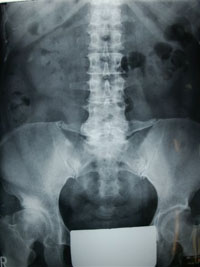

背骨を作りあげている脊椎には、骨同士に囲まれた空間があり、そこを脳から出た脊髄神経の束が通っています。その空間を脊柱管と呼んでいます。

脊柱間狭窄症は、その神経が通っている脊柱管が、靭帯や骨、関節、椎間板が老化して形が変わったために狭くなり、神経根や脊髄神経が圧迫されて痛みを感じる病気です。

症状としては脊柱管が狭くなるので神経が圧迫され、腰痛や下肢痛、しびれを感じます。

馬尾神経が圧迫されると歩いた時に腰痛や両下肢痛、しびれが強くなり、歩けなくなってしまいます。しばらく休憩するとまた歩けるようになる間欠性跛行が特徴です。